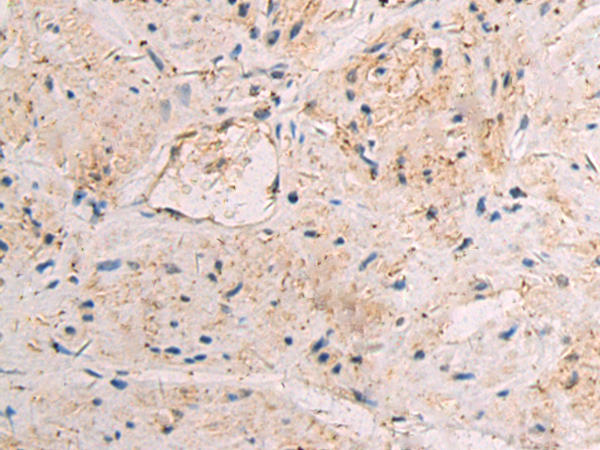

Applications: |

IHC |

IHC positive control: |

Human breast carcinoma tissue |

IHC Recommend dilution: |

50-100 |